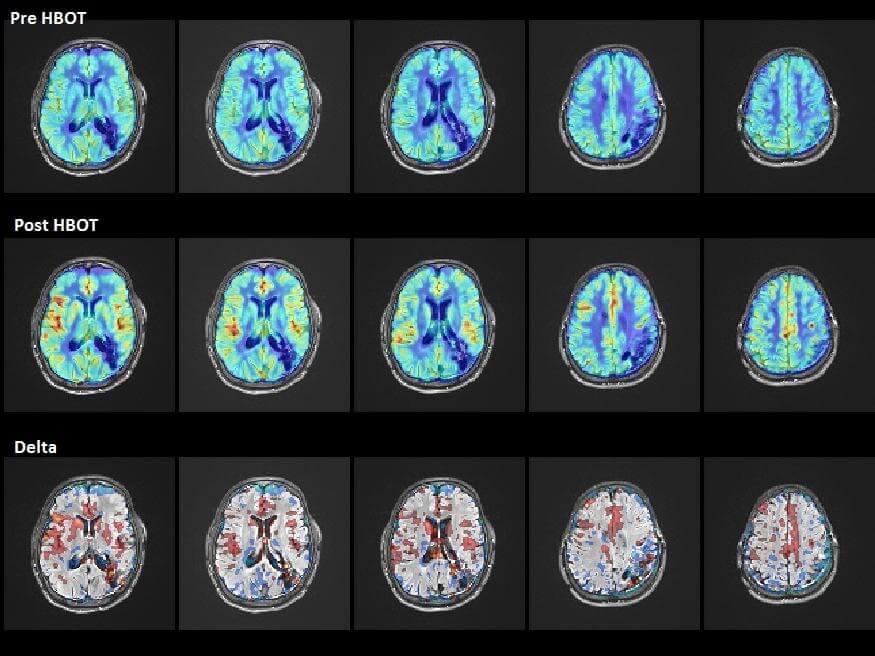

وبينما كانت التحسينات الخارجية التي يمكن ملاحظتها واضحة، لم تكن هذه هي النتائج الإيجابية الوحيدة. فقد تم تقييم المرضى بشكل أكبر باستخدام تصوير التمثيل الغذائي للدماغ (SPECT) لفحص نشاط الدماغ أثناء العلاج بالأكسجين عالي الضغط. وأظهر التصوير بشكل واضح أن آفات التمثيل الغذائي في الدماغ التي لوحظت سابقاً في مناطق معينة قد اختفت. وكان تجديد الخلايا العصبية في المرضى المزمنين في المراحل المتأخرة مشجعاً بشكل خاص. وعموماً، خلصت الدراسة إلى أن النتيجة “تشير إلى أن زيادة تركيز الأكسجين في البلازما بالأكسجين عالي الضغط هو وسيلة فعّالة لتوصيل الأكسجين الكافي إلى الدماغ لإصلاح الأنسجة.”

يظهر التصوير بالرنين المغناطيسي تحسناً في تدفق الدم في الدماغ بعد العلاج بالأكسجين عالي الضغط في مريض السكتة الدماغية.